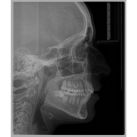

4- Los estudios complementarios previos que si o si necesito son: radiografía panorámica y telerradiografía de perfil. En casos más complejos puede ser

necesario una telerradiografía frontal o una tomografía.